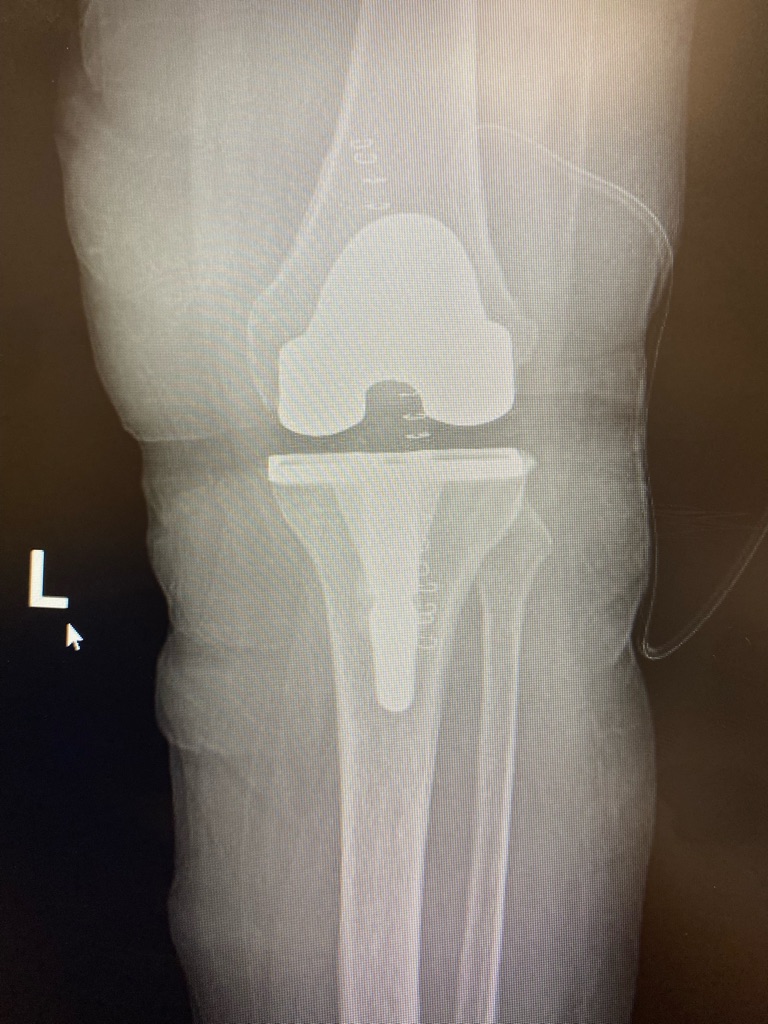

Knee replacement